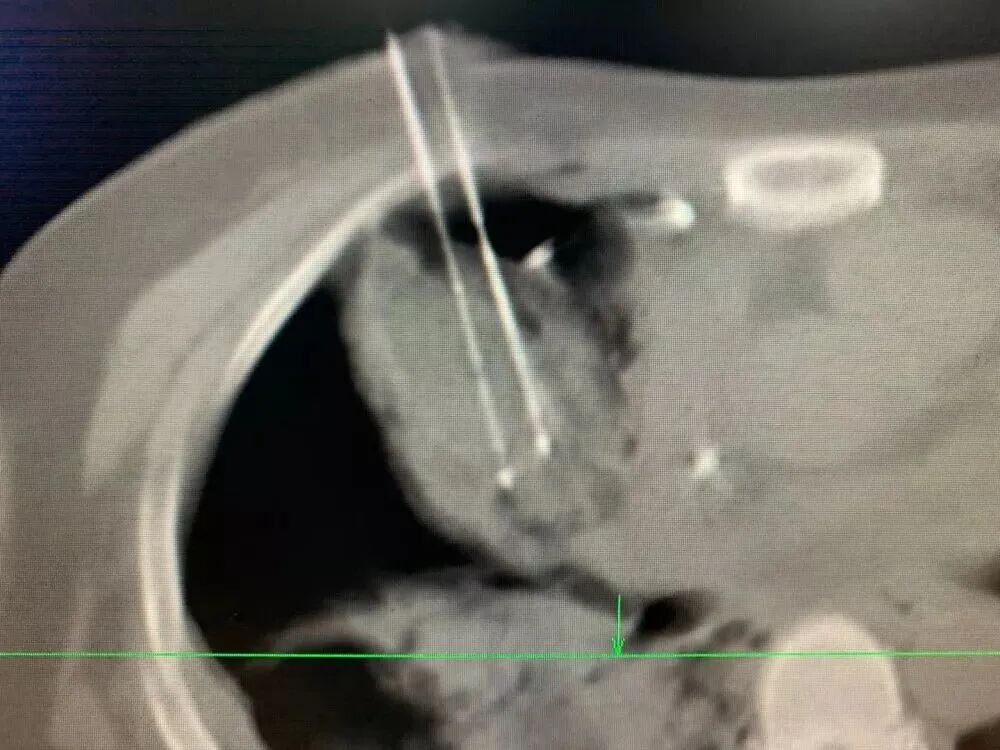

手术中,我用一根冷冻针“钓”住肿瘤,像收起鱼线那样,慢慢把它从心脏附近牵引到更安全的位置,再实施冷冻消融。整个过程必须极度谨慎,因为心脏周围血管丰富,稍有不慎就可能引发大出血。

这不仅考验医生的技术,更考验经验和心理素质。既高度集中精神将肿瘤移出消融,也要时刻紧盯着心脏等重要器官是否正常运行。整个手术不允许有丝毫的偏差,耗时一个多小时才结束。

类似的情况还包括长在肺门附近的结节,位置也非常棘手。借助冷冻固定和“钓鱼”技巧,使结节远离肺门大血管,再插入活检针和冷冻针,就能安全、彻底地消灭它。